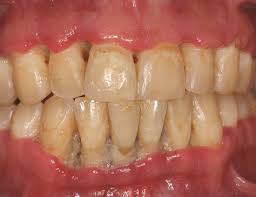

Treatment should include the alleviation ol the acute symptoms and the correction ol the underlying chronic gingival disease. If nug is left untreated it can progress to the more severe forms. Treatment is gentle debridement improved oral hygiene mouth rinses supportive care and if debridement must be delayed antibiotics. Sequela of single or multiple episodes of necrotizing ulcerative gingivitis nug signs. Characterized by necrosis of gingival tissues and loss of periodontal ligament and alveolar bone see fig.

It has an acute clinical presentation with the distinctive characteristics of rapid onset of interdental gingival necrosis gingival pain bleeding and halitosis. Acute necrotizing ulcerative gingivitis anug occurs most frequently in smokers and debilitated patients who are under stress. Treatment of acute necrotizing ulcerative gingivitis. Acute necrotizing ulcerative gingivitis anug has been generally considered as a gingivitis. Acute necrotizing ulcerative gingivitis definition acute necrotizing ulcerative gingivitis or anug is characterized as a plymicrobial infection of the patient s gums that normally leads to bleeding inflammation necrotic gum tissue and deep ulcerations.